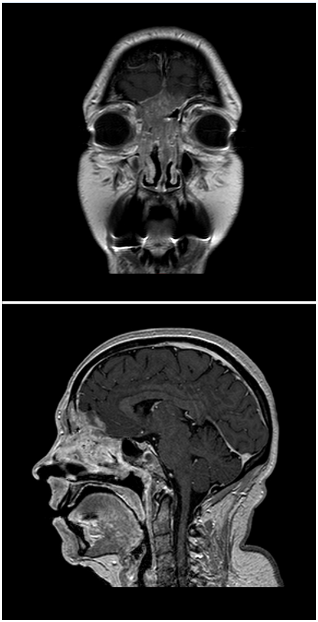

A 52-year-old Caucasian female with complaints of chronic nasal obstruction and anosmia was conservative treated for 2years. The patient was sent to our tertiary care center after developing a forehead swelling and decreased visual acuity. Contrast-enhanced CT-Scan and MRI (Figure 1 & 2) showed a large nasal cavity tumor, achieving both frontal sinuses, with bone expansion and erosion, and infiltrating the anterior cranial fossa. A nasal endoscopic guided biopsy was performed under general anesthesia and the histologic findings revealed a sinonasal undifferentiated carcinoma (SNUC). According to the current TNM classification of sinonasal tumors, the neoplasm was classified as cT4b. Further staging excluded cervical or distant metastases. This tumor was also classified as C, according to the Kadish System. After a promptly case presentation on our tumor board, and because an R0 resection would not be possible, a decision was made against a surgical treatment. A primary radiochemotherapy was recommended and initiated.

Figure 2 SNUC infiltrating the anterior cranial fossa (contrast-enhanced MRI, T1).